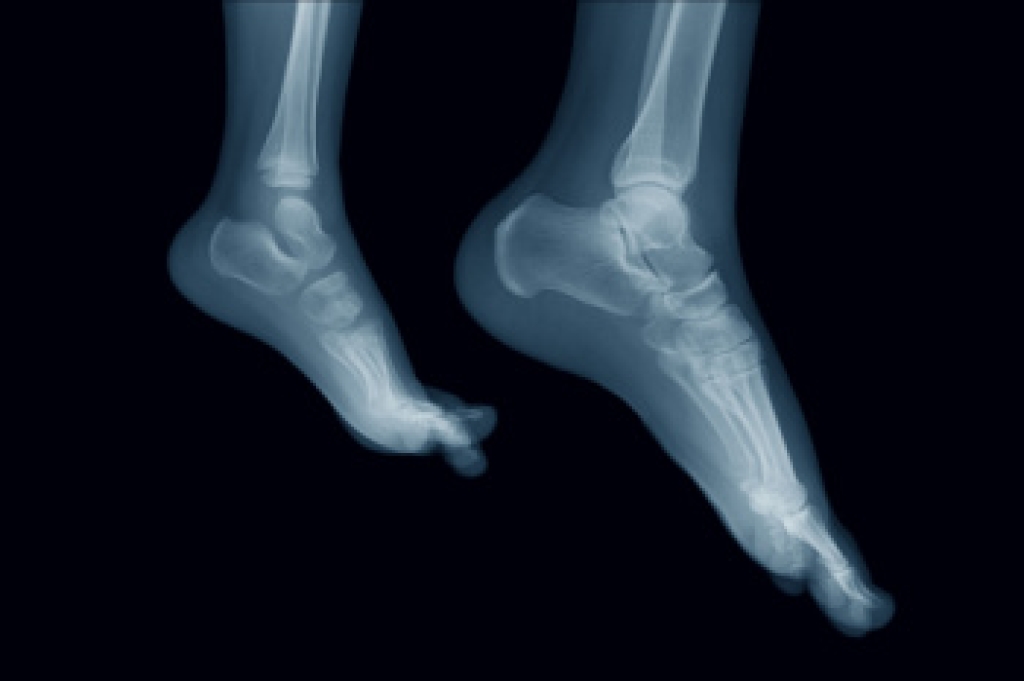

Arthritis is a joint disorder that involves the inflammation of different joints in your body, such as those in your feet. Arthritis is often caused by a degenerative joint disease and causes mild to severe pain in all affected areas. In addition to this, swelling and stiffness in the affected joints can also be a common symptom of arthritis.